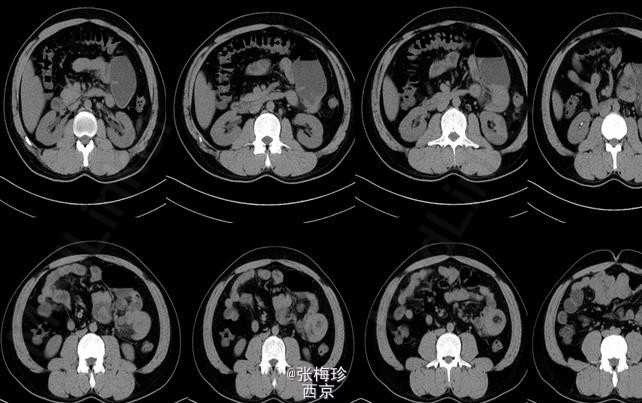

临床一例Meckel憩室

患者男性,30岁,2周前无明显诱因出现肚脐周围闷痛为绞痛伴恶心。

Meckel憩室 处理;手术治疗,解除梗阻并切除憩室

Meckel憩室及其并发症并无特殊的临床表现,与其他急腹症很难鉴别